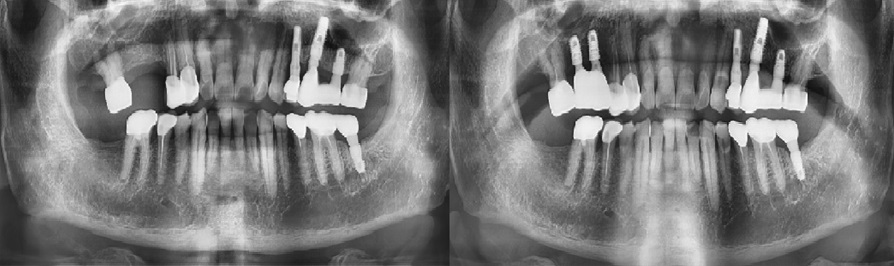

치료전후사진